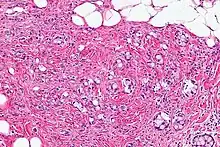

Micrograph showing a goblet cell carcinoid. H&E stain.

Micrograph of a goblet cell carcinoid. H&E stain.

GCCs are diagnosed by pathology. They have a characteristic biphasic appearance which includes (1) goblet cell-like cells, and (2) neuroendocrine-type nuclear chromatin (stippled chromatin).